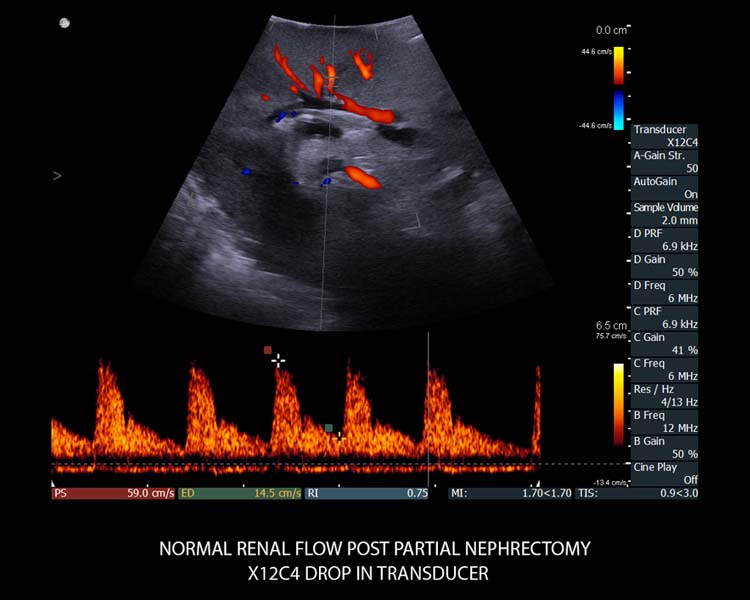

- Hochauflösende Echtzeit-Bildgebung mit herausragenden anatomischen Details.

- Unmittelbare, automatisch optimierte Bildgebung mit No-touch Autogain und Auto Focus – hier sind keine Einstellungen erforderlich.